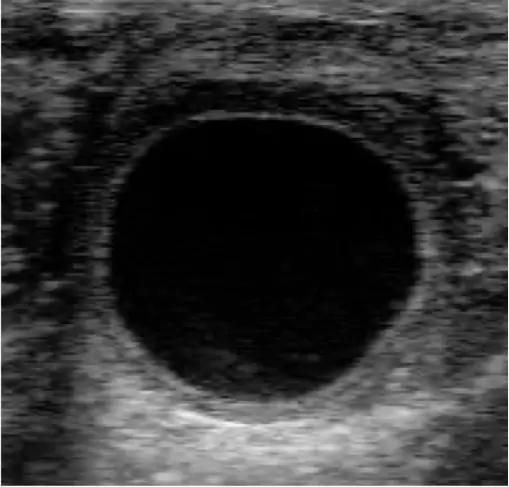

Данные с источника: "На протяжении десятилетий женщины могли узнать, беременны ли они в считанные минуты, используя недорогие наборы для тестирования на основе мочи в уединении и удобстве своих собственных домов.

К сожалению, то же самое не относится к коровам. В то время как многие альтернативы пальпации развивались на протяжении многих лет, быстрый, удобный набор для тестирования на беременность на ферме оставался неуловимым.

Теперь IDEXX Laboratories, Inc. вывела на рынок тест на беременность Alertys OnFarm, который можно использовать для определения беременности уже через 28 дней после разведения или через 70 дней после отела. Результаты доступны через 5-20 минут.

Alertys оценивает беременность с использованием образца цельной крови, сыворотки или плазмы. Он определяет беременность путем измерения связанных с беременностью гликопротеинов (ПАГ), которые вырабатываются только в присутствии эмбриона или плода. И, как и человеческий тест, он указывает на беременность с чтением двух розовых линий.